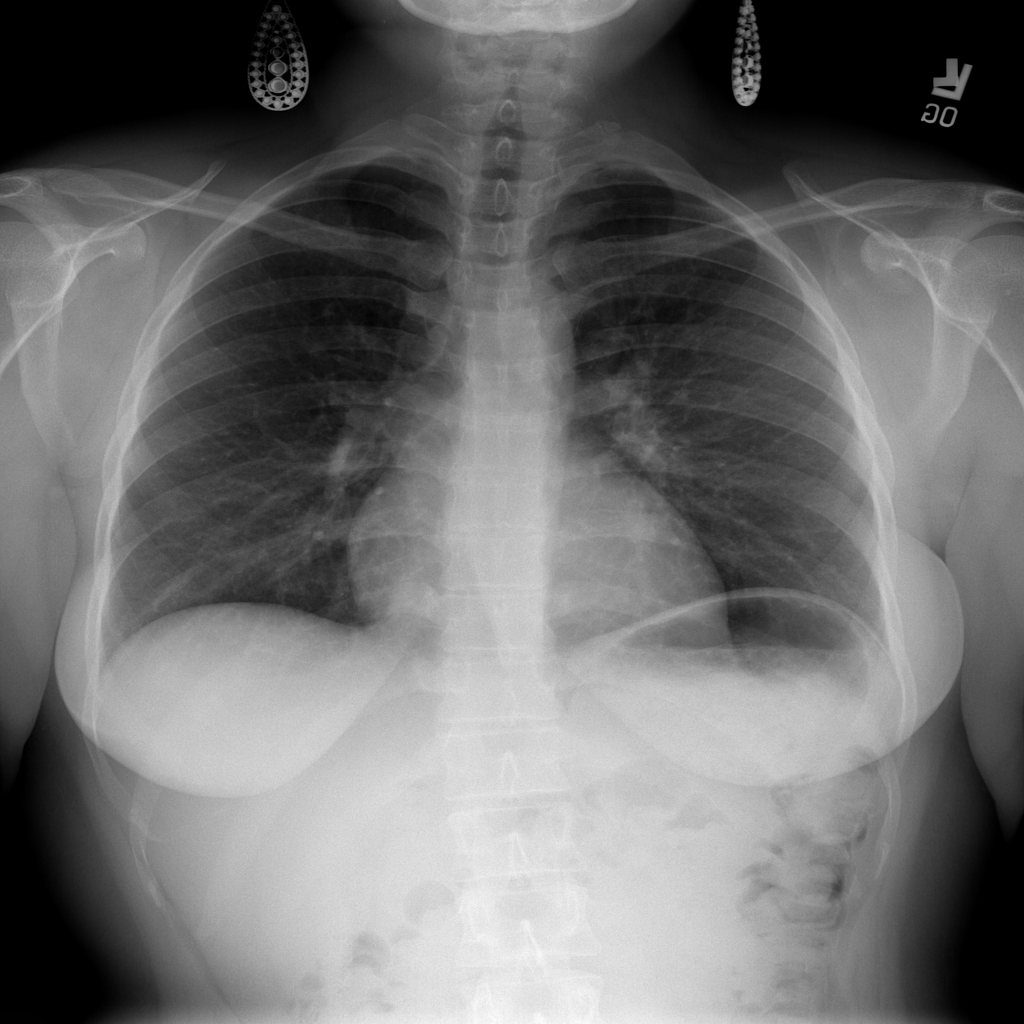

PAT-B3C3 · IMG-001Pneumonia

PAT-B3C3 · IMG-001

PA